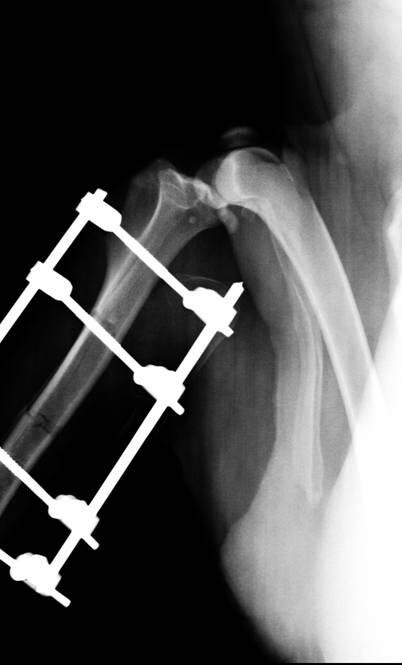

2 外固定支架

骨折后外固定支架在X光下图片。